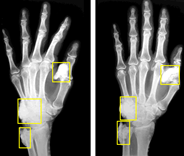

Wrist Bone

Wrist Bone Trauma AI

Machine Learning-Aided Diagnosis Enhances Human Detection of Perilunate Dislocations.

Peri-articular Calcification

Detection and characterization using deep learning for quantification and staging.